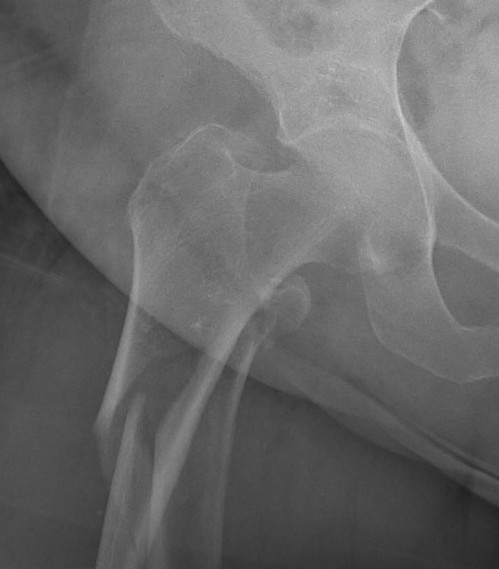

Definition

Fracture below lesser trochanter

Proximal 5 cm femoral shaft

1. Proximal fragment flexed, in varus and externally rotated with distal fragment adducted

- iliopsoas flexes proximal fragment

- abductors cause varus of proximal fragment

- external rotators rotate proximal fragment

- adductors medialize distal fragment